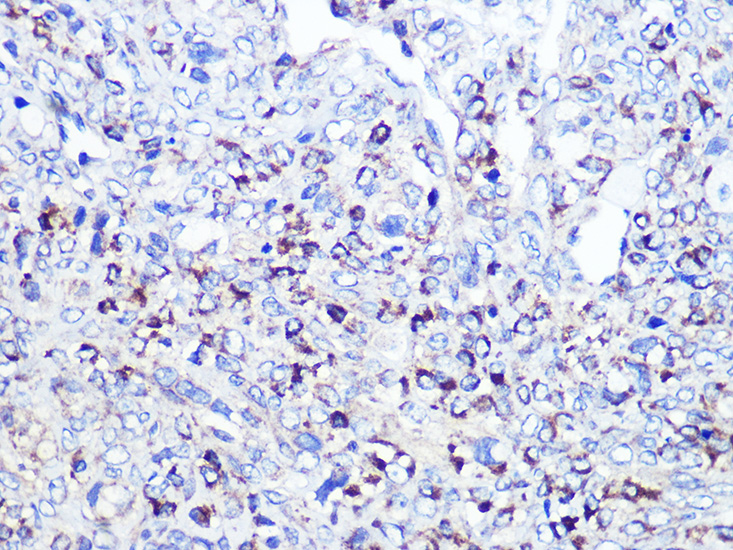

Immunohistochemistry of paraffin-embedded Human oophoroma using CD68 at dilution of 1:100 (40x lens).